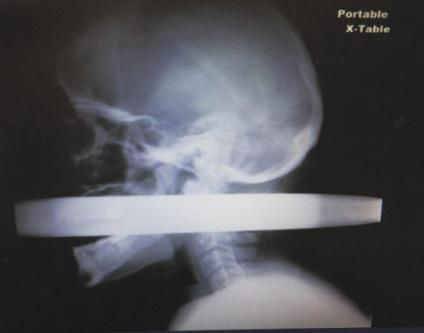

1、护栏穿颈,竟然不痛?

拉斯维加斯28岁男性Andrew Linn,车祸中被2英寸厚度的金属护栏经口穿过,从颈部穿出。

贯通伤没啥奇怪,但是这哥们儿的接诊外科医生Jay Coates描述,患者来得时候非常平静而且并不感觉疼痛。之后这根杆子被成功取出,而且没有碰伤颈动脉和颈静脉。